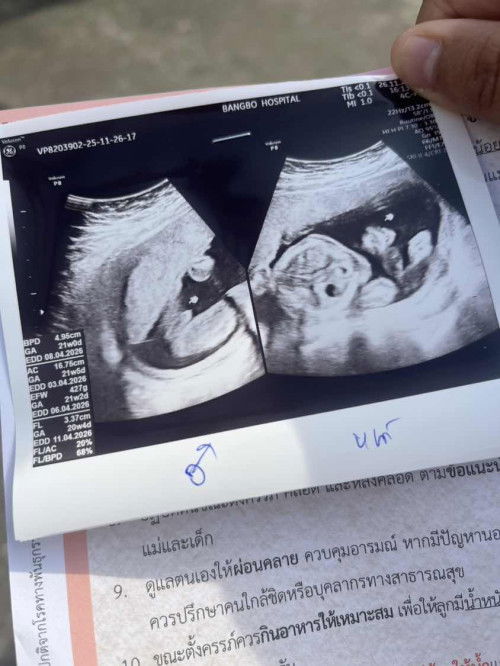

แม่ๆแบบนี้ใช่ลูกชายไหมคะแต่ป้าหมอบอกว่าผู้ชาย